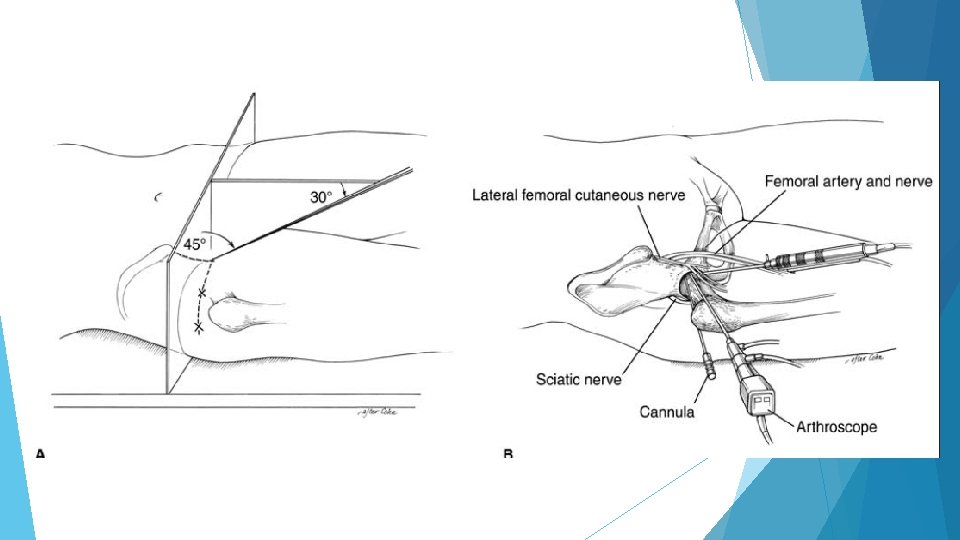

Hip Arthroscopy